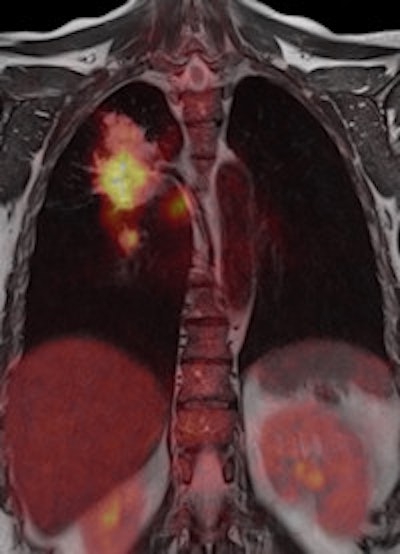

When the doors of the ECR 2011 technical exhibition burst opened this morning, a host of surprises and innovations awaited congress attendees. Arguably the biggest highlight of all is the first PET/MR system ever displayed at the Austria Center, and it looks certain to attract massive attention and interest over the next four days.

A combination of MRI and PET has long been considered as the logical next step in the evolution of imaging modalities, but industry has struggled to deal with the formidable technical challenges of achieving a happy marriage between the two approaches, notably the difficulties of developing a PET detector capable of coping with the powerful static and dynamic magnetic fields generated by the MR coils. GE Healthcare made the first important move in developing the software needed to integrate data acquired through sequential scans made using the two modalities. Then Philips brought the two main items of hardware alongside each other, linked by a revolving table for easy patient transfer, and the company installed the first European system in a hospital in Geneva in April 2010. Now Siemens' engineers have successfully merged the two modalities in a single unit, dubbed the Biograph mMR, which the vendor plans to launch commercially later this year.

In the meantime, radiologists will be able to examine the prototype on display in the technical exhibition, and if they are lucky, they will get to talk to Dr. Markus Schwaiger and his colleagues from the Klinikum rechts der Isar at the Technical University in Munich. The group has been given the privilege of putting the new machine through its paces.

Dr. Alexander Drzezga, from the university's department of nuclear medicine, has been responsible for setting up the system, which was delivered in November 2010. It is currently being used to scan up to five patients a day, but that number is likely to grow as the Munich team explores the limits of the unit's clinical potential. "Many neurological conditions are suitable for evaluation with PET/MR, including neurodegenerative disorders, dementia, epilepsy, and brain tumors. With regard to evaluation of the cardiac system, combined imaging of PET and MR may also show diagnostic advantages, while inflammation and vascular conditions are also areas of interest," he explained.

Drzezga believes that combining the two modalities offers a number of clinical advantages, not least in eliminating the need for separate diagnostic examinations. Furthermore, the exact anatomical registration of structural and functional/molecular information may improve allocation of suspect findings and improve image quality, for example by motion correction of regions of the body that do not remain rigid during examination. The Munich team will also be exploring how the performance of PET/MR compares with that of PET/CT. There is some evidence that the superior soft-tissue contrast achievable with the newer system will offer significant benefits, even before physicians consider the safety issues involved with any radiation-based imaging technology such as PET/CT, Drzezga suggested.

The Biograph mMR is based on the Verio 3-tesla MR system with a 70-cm bore that provides enough space to position the PET detector ring and its solid-state photodiodes. In getting the two modalities to work alongside each other, the hybrid molecular MR system can scan the whole body in as little as 30 minutes, compared with an hour or more needed for sequential examinations. The machine also incorporates Siemens' TIM (total imaging matrix) technology, which seamlessly integrates multiple coil elements and radiofrequency (RF) channels and can reduce examination times by up to 50%, according to the vendor.